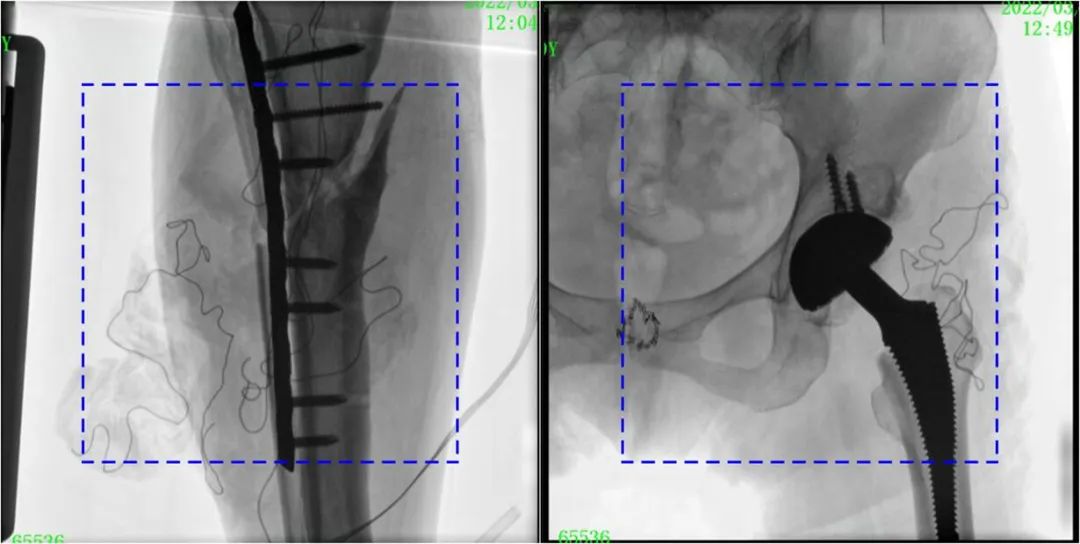

術(shù)中定位準(zhǔn)確、出血量少,術(shù)后影像顯示股骨移位糾正,恢復(fù)良好力線,手術(shù)效果良好。

PLX119C臨床圖像與傳統(tǒng)圖像對比

注:藍(lán)色虛線內(nèi)為傳統(tǒng)21CM×21CM平板的成像區(qū)域。